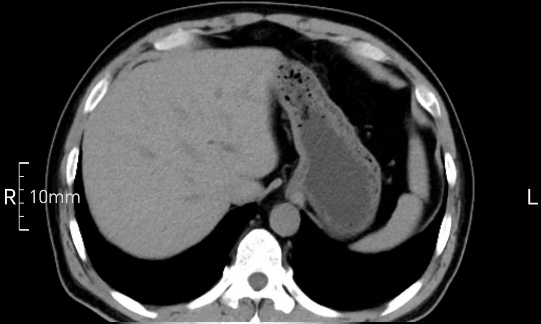

看看下面三幅便知遵醫(yī)囑的重要性。

禁食但檢查前沒(méi)有喝飽,胃未能漲開(kāi),胃壁觀察效果不佳。